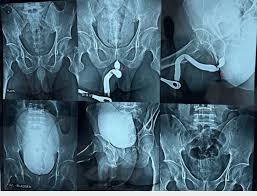

Digital X-Ray Services